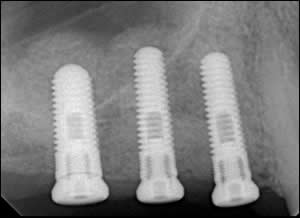

Fig 1: Pre-operative radiograph reveals a low maxillary sinus.

Fig 2: Tracing of the sinus floor